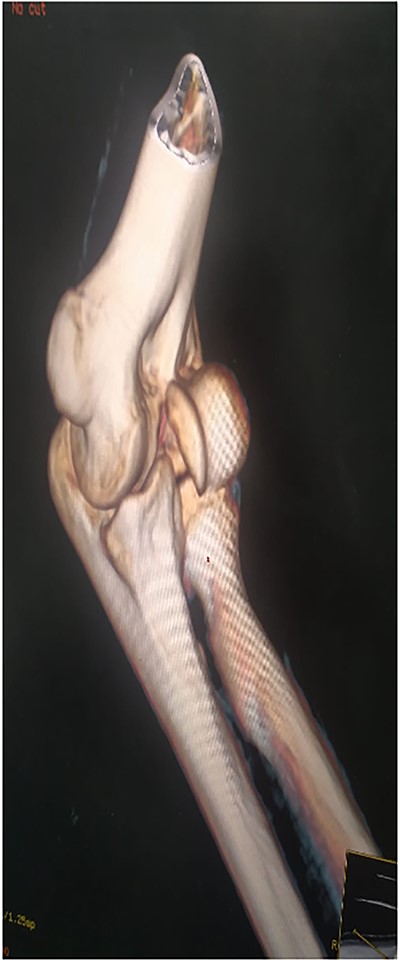

This is a prospective, monocentric study of adult patients undergoing surgical treatment for isolated capitellar fracture. Between 2019 and 2022, we received eight patients (six men and two women) with a mean age of 25 years (18–40 years) who had type I fracture of the capitellum. The dominant arm was affected in six patients (Table 1). All our patient had a fall on an outstretched hand. All fractures were close and isolated without any vascular or neurological damage. Standard AP (anteroposterior), lateral X-rays (Fig. 1) as well as a computed tomography (CT) scan with 3D reconstruction were done for all the patients (Fig. 2). Therefore, fractures with trochlea involvement were excluded.